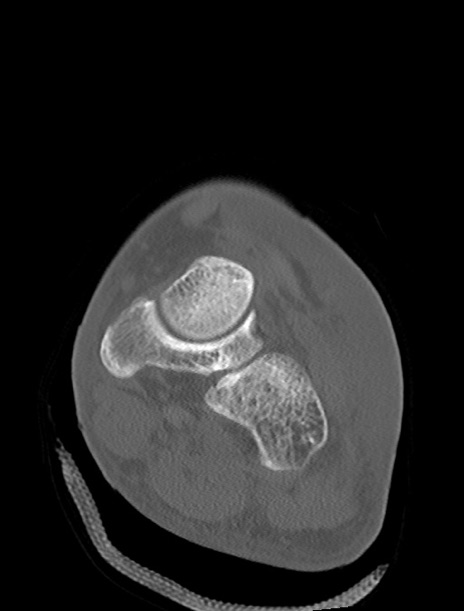

症例37 左足関節CT(冠状断像)

左足関節CT

横断像